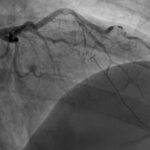

This case report discusses a 36-year-old male who presented to the emergency department with an atypical story for acute coronary syndrome (ACS). Initially, the patient was felt to have a non-diagnostic electrocardiogram (ECG). Once the laboratory test results were obtained and the initial high-sensitivity troponin was noted to be elevated, the initial ECG was again reviewed. The patient was felt this time to have an abnormal ECG, demonstrating borderline ST elevation in leads I, aVL, and V2-V5. The interventional cardiologist on call was contacted, and the cardiac catheterization lab was activated. Upon left heart catheterization, the patient was found to have a spontaneous coronary artery dissection (SCAD) of the distal left anterior descending (LAD) artery. Post-catheterization, the patient was observed on cardiac telemetry and started on dual antiplatelet therapy. Echocardiogram revealed a preserved ejection fraction (EF), but hypokinesis of the apical anterior, anterolateral, inferior, and apical myocardium. The patient was discharged within 48 hours without any complications.